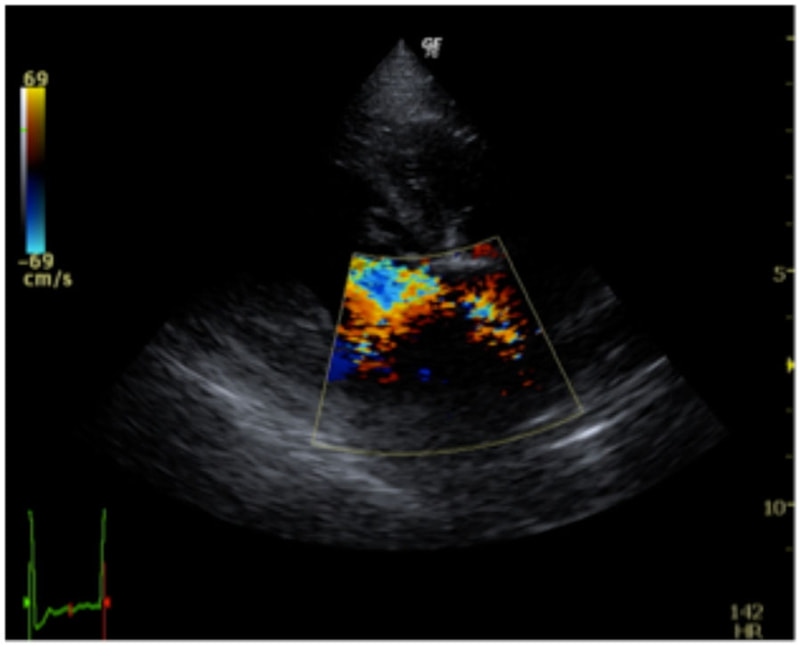

C:超音波 僧帽弁逆流のカラードップラー画像

左側胸壁心尖部領域を最強点とするLevine 5/6の収縮期性心雑音が聴取された。安静時にも咳が認められる。胸部レントゲン検査において重度の心拡大が及び肺水腫が認められた。超音波検査では、重度の僧帽弁閉鎖不全、三尖弁閉鎖不全が認められた。三尖弁逆流速度から肺高血圧症が示唆された。ACE阻害薬、ピモベンダン、硝酸イソソルビド徐放剤、ベラプロストナトリウム、利尿剤としてフロセミド及びスピロノラクトンを用いて治療を行っている。